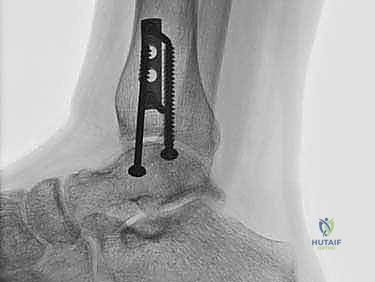

2. الزرع الغضروفي العظمي الذاتي (OATS / Autograft): وهو محور حديثنا والتقنية الذهبية التي يبدع فيها الأستاذ الدكتور محمد هطيف لعلاج الآفات المتوسطة والكبيرة.

الغوص العميق: تقنية الزرع الغضروفي العظمي الذاتي (OATS) خطوة بخطوة

تُعد تقنية OATS (Osteochondral Autograft Transfer System) بمثابة "زراعة أعضاء دقيقة" داخل المفصل. الفكرة الأساسية هي أخذ أسطوانة صغيرة من العظم والغضروف السليم من منطقة لا تحمل وزناً كبيراً في جسم المريض (غالباً من مفصل الركبة)، ونقلها وزرعها في مكان الآفة التالفة في الكاحل.

هذه التقنية توفر "غضروفاً زجاجياً حقيقياً" (Hyaline Cartilage)، وهو نفس نوع الغضروف الأصلي الذي خُلق به الإنسان، مما يضمن متانة وقدرة على تحمل الأوزان لا يوفرها أي علاج آخر.